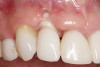

Fig 3. Initial buccal view of tooth No. 7.

Figure 3

Fig 4. Radiograph showing root fracture and apical lesion of the tooth (No. 7).

Figure 4